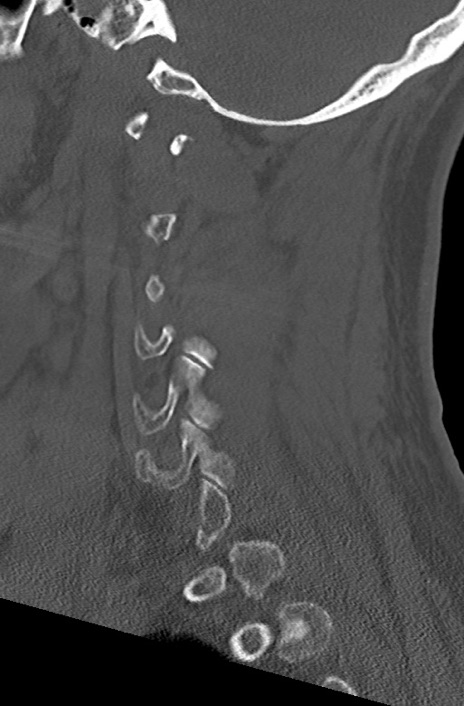

頚椎CT

矢状断像と横断像